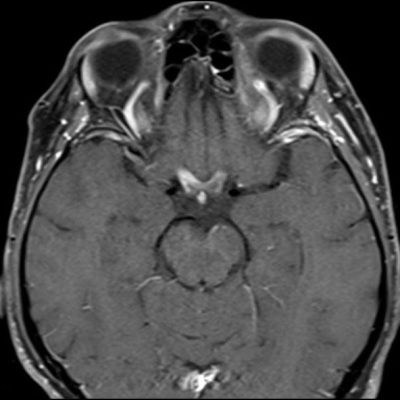

- (B) Orbita MRG’de aksiyel yağ baskılı T1A’da optik sinir prekiazmatik segmenti (oklar) gösterilmiş olup sırası ile aksiyel ve koronal post-kontrast yağ baskılı T1A görüntülerde bilateral optik sinir prekiazmatik segmentte kontrast tutulumu dikkati çekmektedir (oklar ve daire).

- Optik nörit varlığında özellikle optik kiazma ve posterior optik sinir tutulumu görülür ve bilateral olabilir.

- MS’de optik nörit radyolojik tutulumu daha fokal iken NMO spektrum bozukluğu ve MOGAD’de genellikle daha yaygındır. MOGAD, NMO’ya kıyasla daha anterior kısmı etkileme eğilimindedir.